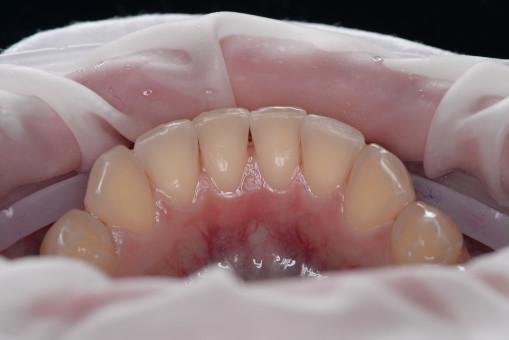

А прежде, чем вы посмотрите фотографии «до» и «после» лечения слизистой оболочки полости рта, проведенных в нашей клинике, хочу поблагодарить большое количество наших пациентов, которые поверили, прониклись нашей концепцией, и мы вместе, именно вместе победили болезни десны, гингивит и пародонтит!

До/после лечения